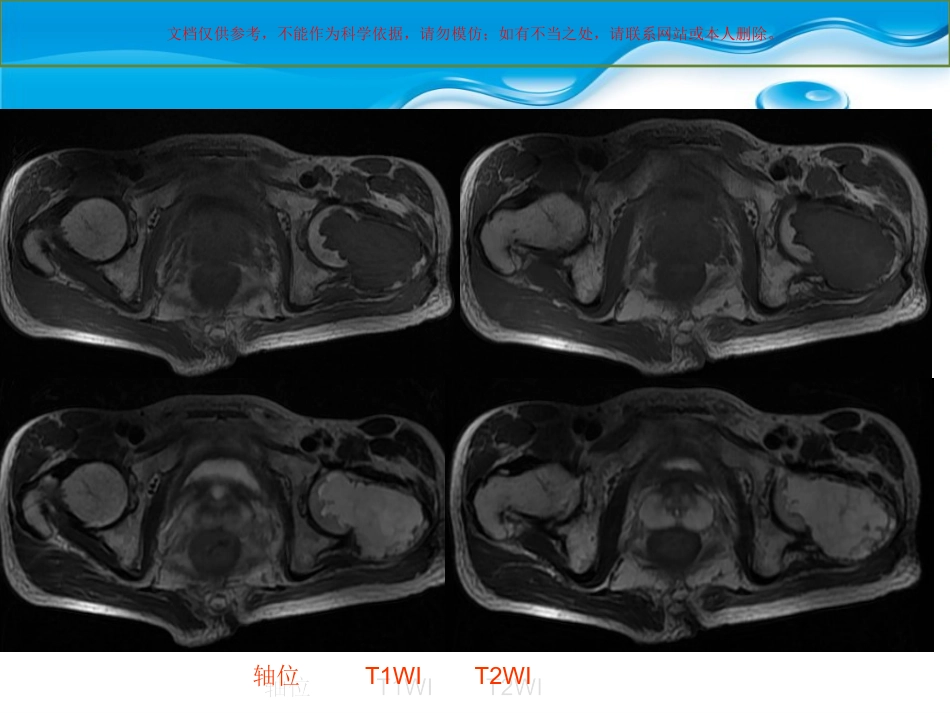

文档仅供参考,不能作为科学依据,请勿模仿;如有不当之处,请联系网站或本人删除。患者一般信息男性56岁3年前无明显诱因出现左髋部疼痛,曾于当地诊所治疗,外用药物(具体不详),近1月自觉疼痛加重,伴跛行,遂往医院就诊;专科检查:左髋部外侧较健侧膨隆,局部压痛(+),髋关节活动受限,皮肤无红肿,左侧腹股沟区淋巴结未触及。文档仅供参考,不能作为科学依据,请勿模仿;如有不当之处,请联系网站或本人删除。文档仅供参考,不能作为科学依据,请勿模仿;如有不当之处,请联系网站或本人删除。轴位T1WIT2WI轴位T1WIT2WI文档仅供参考,不能作为科学依据,请勿模仿;如有不当之处,请联系网站或本人删除。T1WIT2WIT1WIT2WI文档仅供参考,不能作为科学依据,请勿模仿;如有不当之处,请联系网站或本人删除。STIRSTIR文档仅供参考,不能作为科学依据,请勿模仿;如有不当之处,请联系网站或本人删除。轴位T1WIT1WI/C轴位T1WIT1WI/C文档仅供参考,不能作为科学依据,请勿模仿;如有不当之处,请联系网站或本人删除。冠位T1WI/C冠位T1WI/C文档仅供参考,不能作为科学依据,请勿模仿;如有不当之处,请联系网站或本人删除。•MR诊断意见:左侧股骨头、颈及股骨干上端异常信号影,考虑良性骨肿瘤或骨肿瘤样病变,骨巨细胞瘤可能。文档仅供参考,不能作为科学依据,请勿模仿;如有不当之处,请联系网站或本人删除。文档仅供参考,不能作为科学依据,请勿模仿;如有不当之处,请联系网站或本人删除。•手术记录:左侧股骨颈及股骨粗隆部膨隆,后侧为重,骨皮质菲薄不完整,微波灭活后开骨窗刮除白色粘液状肿瘤组织,有软骨光泽。病变累及股骨头下,瘤腔内可见骨性分隔。•术后病理:软骨粘液样纤维瘤文档仅供参考,不能作为科学依据,请勿模仿;如有不当之处,请联系网站或本人删除。•软骨粘液样纤维瘤(Chondromyxoidfibroma)又称纤维粘液样软骨瘤,是一种较少见的良性骨肿瘤,起源于软骨组织,是良性软骨性肿瘤中最少见的一种。WHO统计,占原发性骨肿瘤的1.04%,占良性骨肿瘤的2.31%[1]。由Jaff和Lichtenstein首先报道了此病,并对病理组织学做了详细描述,并予以命名。•【1】王玉凯,主编骨肿瘤X线诊断学:M:北京:人民卫生出版社.1995:106文档仅供参考,不能作为科学依据,请勿模仿;如有不当之处,请联系网站或本人删除。•CMF病理基础:大体所见肿瘤呈圆形或椭圆形,偶尔呈分叶状,切面呈黄白色或灰白色,边缘清楚。瘤内可见纤维条索区、粘液样区、透明软骨区三者呈不同比例相间存在。镜下瘤细胞核多呈星形、椭圆形或梭形,瘤细胞常较为密集,主要由两种基质存在,1、致密的软骨样基质,嗜碱性;2、疏松的粘液样基质,嗜酸性,多以后者为主。粘液样组织可纤维化或变为软骨样组织。【2】免疫组化s-100(+),显示其为软骨类肿瘤。【2】曲亚罡等软骨粘液样纤维瘤CT诊断[J]吉林医学,2004;2:27;文档仅供参考,不能作为科学依据,请勿模仿;如有不当之处,请联系网站或本人删除。•肿瘤有时可见钙化或出血区。但往往钙化较少见,有学者解释为本病是从粘液样组织发生向软骨及胶原纤维转化的特性,而非源于软骨组织后发生粘液样变。【2】•【2】曲亚罡等软骨粘液样纤维瘤CT诊断[J]吉林医学,2004;2:27;文档仅供参考,不能作为科学依据,请勿模仿;如有不当之处,请联系网站或本人删除。•临床资料:本病男性发病率多于女性,约为1.9:1,年龄大多在10-30,占73.2%。发病部位多见长管状骨的干骺端,尤以下肢多见,另外本病也可发生于其他部位,如短管状骨、扁骨、不规则骨等。•本病临床症状较轻微,生长缓慢,主要表现为局部间歇性疼痛,病变范围较大时,可能影响关节功能。表面皮肤多无变化。文档仅供参考,不能作为科学依据,请勿模仿;如有不当之处,请联系网站或本人删除。影像表现•X线:本病多呈偏心性、膨胀性生长,可呈单房或多房性透亮区,肿瘤内可见粗细不一的骨性间隔,数目多少不等,骨皮质菲薄,亦可中断,该病很少有骨膜反应。一般其内缘具有较厚的骨质硬化,其外缘多呈扇形、分叶状。【3】【3】骨肿瘤影像学段承祥、王晨光、李健丁主编,北京科学出版社,2004.7文...